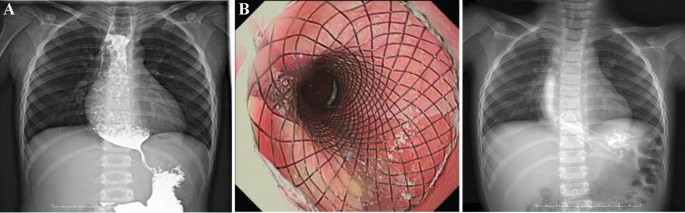

The esophagus of all 14 pediatric patients were imaged using contrast upper gastrointestinal tract radiography, of whom 10 with chemically corrosive esophageal stricture showed that the contrast medium passed through the esophagus slowly and unveiled one or more segments of stenosis along the course of the esophagus, with dilated portions at the upper part of the esophagus, 2 cases of achalasia of cardia featured the stenosis of the lower esophagus as unique beak-like changes with the difficulty in passing the contrast medium (Fig. 4A), 1 case of esophageal perforation caused by balloon dilatation of esophageal stricture (Fig. 5A) showed that the contrast medium had infiltrated the mediastinum (Fig. 5B), and 1 case had esophageal perforation after peroral endoscopic myotomy (POEM) (Fig. 6A).

Stent placement in a patient with achalasia of cardia (case 12). (A) The upper gastrointestinal tract radiography showed a beak-like change, suggesting it was difficult for the barium to pass through before surgery; (B) A stent was placed and expanded as the patient body temperature rose; (C) Upper gastrointestinal tract radiography showed normal passing through of the contrast agent after stent placement.

Stent placement in a patient with an EBD-induced esophageal perforation (case 14). (A) Esophageal perforation secondary to endoscopic balloon dilatation, the upper oral mucosa of the stricture was torn and bleeding; (B) Stent malapposition occurred 5 days after the first stent implantation; upper gastrointestinal tract radiography revealed that contrast medium infiltrated the mediastinum; (C) The original esophageal stent was replaced by a redesigned stent with larger upper bell mouth; (D) After the second esophageal stent was placed, upper gastrointestinal tract radiography revealed that the fistula was plugged, without contrast medium extravasating.

Stent placement in a patient with esophageal perforation after POEM (case 13). (A) A stent was placed after esophageal perforation was found during POEM, but stent migration occurred after 7 days; (B) After the stent position was adjusted under the endoscope, gastrointestinal tract radiography did not reveal extravasation of contrast medium; (C) The fistula was closed after the stent was removed 1.5 months later.

Two patients with achalasia of cardia (cases 11 and 12) showed remarkable improvement in the symptoms of vomiting (Fig. 4B,C) without the need for further stent placement. Two patients (cases 2 and 11) presented symptoms of vomiting and chest pain 2–3 days after stenting, which were relieved by conservative management without stent removal. Three patients (cases 5, 9 and 10) developed restenosis 3 months after stent removal, but the degree of stenosis had been significantly mitigated compared to before stenting and the lumens at the narrowing were significantly enlarged, with improvement in swallowing difficulty after the new stents were placed (Fig. 7B).

The child with esophageal perforation after POEM (case 13) was given an esophageal stent (Fig. 6A), but 7 days after its placement, the patient developed stent migration, which was dealt with by an adjustment of the stent position under endoscopy, consequently leading to the closure of the fistula one and half months later (Fig. 6B,C). The child with esophageal perforation (case 14) underwent closed thoracic drainage for esophageal mediastinal fistula and then received empyema exploration, with esophageal stent placement. However, the patient was found to have stent malapposition 5 days after the operation (Fig. 5B), which required the removal of the original stent and its replacement with an esophageal stent with a larger upper bell mouth (Fig. 5C,D). Two months later, the stent was removed, the fistula healed and the stenosis disappeared.